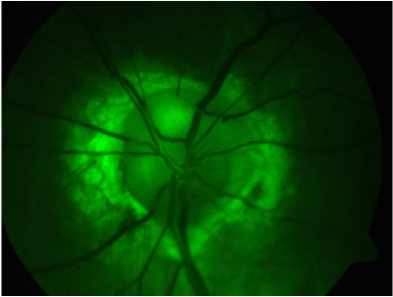

On examination her BCVA were (Figure 1) RE: 6/5+2 and (Figure 2) LE: 6/9-3, her extraocular movements were normal. There were no phorias or tropias and there was no nystagmus. Her colour vision tested with Ishihara’s colour plates was normal. The anterior segments were unremarkable and there was no RAPD. Intra ocular pressures were RE: 16 mm Hg and LE 18 mm Hg.

Figure 1 Right eye.

RE: Normal (Figures 1 & Figure 3).